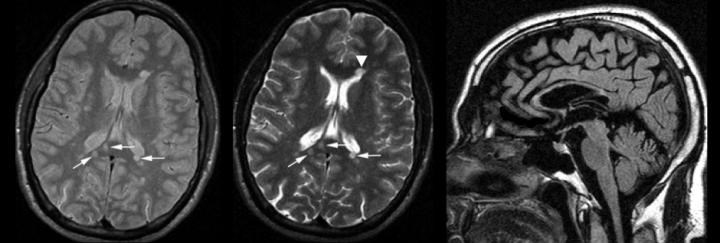

Tipik lezyon lokalizasyonları

- Korpus kallozum lezyonları

- Periventriküler lezyonlar

- Beyin sapı / infratentoriyal lezyonlar

- Jukstakortikal lezyonlar

- Spinal kord lezyonları

Bu bölgelerdeki örnek lezyon alanları, MRG üzerinde İMG – MRG-1’den İMG – MRG-6’ya kadar olan görsellerde gösterilmiştir.

İMG – MRG-1: Tipik T2 lezyonları.

İMG – MRG-2: Korpus kallozum ve periventriküler lezyonlar.

İMG – MRG-3: Beyin sapı / infratentoriyal yerleşim.

İMG – MRG-4: Periventriküler yerleşimli lezyonlar.